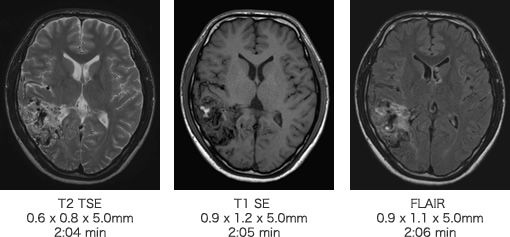

画像例(頭部領域)